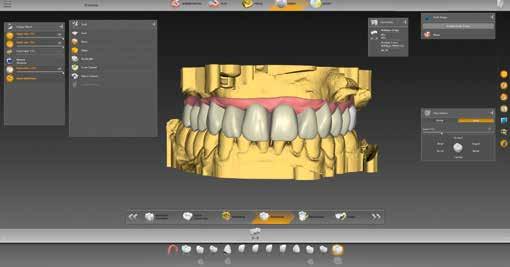

15–17. ábrák: A szoftver tervjavaslata okkluzális, labiális és szagittális irányból. 18. ábra

18–21. ábrák: A hidak labiális és okkluzális nézete – felül leplezve, alul fél-átlátszóan megjelenítve, így látható a váz formája. 22. ábra

ábra). A képernyő jobb oldalán megfigyelhető. Berajzoltuk az adhezív sapkák széleit (11–12. ábrák), ez automatikusan, vagy kézzel is történhet. Végül meghatároztuk a behelyezési irányt. A tervezés során meg kellett adnunk alapvető paramétereket, például a vastagságot illetően (13. ábra). A kívánt anatómiai formát számos lehetőség közül választhatjuk ki a könyvtárból (14. ábra). Az eddig beolvasott adatok és a terv paraméterei alapján a szoftver javasol egy megoldási variációt, három híddal és gingivarésszel (15–21. ábrák). Ez a továbbiakban egyedileg módosítható, mielőtt az inLab CAM szoftverbe küldjük (22–26. ábrák).